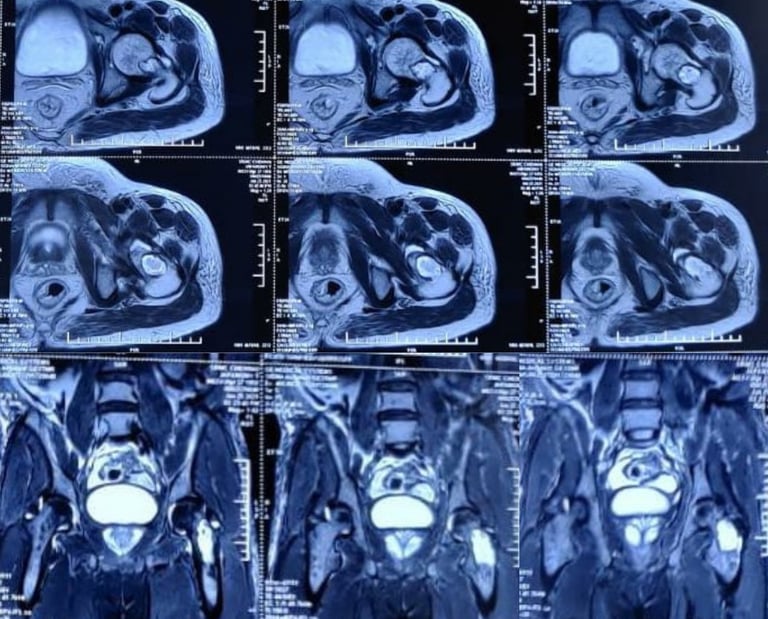

Inverted horn myositis ossificans circumscripta in the pelvis and bilateral adductors

Myositis ossificans is a benign ossifying lesion which can affect any soft tissue including subcutaneous fat, tendons, muscles and nerves. The common locations include the elbow, hip and knee. The pelvis is an extremely rare site for myositis ossificans which has only been described anecdotally in the past. Myositis ossificans involving the adductor muscles- adductor longus or adductor magnus is also an uncommon location, with only a few case reports of its occurrence in athletes. Myositis ossificans involving the adductor longus has been reported to occur in the form of a long, slender, pencil shaped ossification, however the inverted horn is being reported for the first time.